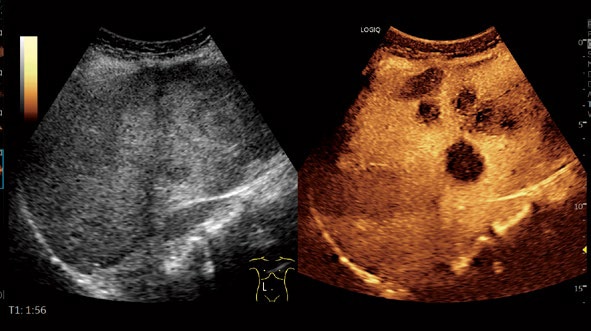

Contrast

独自のコード技術による高い深部感度と空間分解能。

RAW Data保存で、検査後でも染影効果や欠損像の確認まで繰り返し評価可能です。